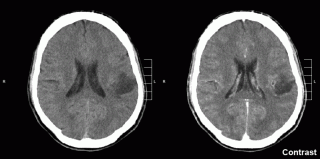

| Glioma image by Mikhail Kalinin, Wikimedia Commons |

Aboody, who is an associate professor at City of Hope in Los Angeles, has a CIRM disease team award to use transplanted neural stem cells (NSCs) as a way of delivering chemotherapy directly to brain tumors (you can read about that award here). When she starts clinical trials, she’ll need to be able to track whether the cells are migrating to the tumor and how long they stick around. She and many other scientists have been developing ways of tracking cells within the body, but so far none had been approved for clinical trials.

In a paper in the September 6 Stem Cells Translational Medicine, Aboody and colleagues reported pre-loading the cells with what a press release from the journal cells “ultra-small, super paramagnetic iron oxide nanoparticles that can then be detected via magnetic resonance imaging (MRI)”.

Basically, they loaded the cell up with an iron-based mixture and injected the cells into animals. They were then able to use MRI to see the cells within the animals. This technique will help Aboody and other scientists tell whether the cells are going where expected in human clinical trials.